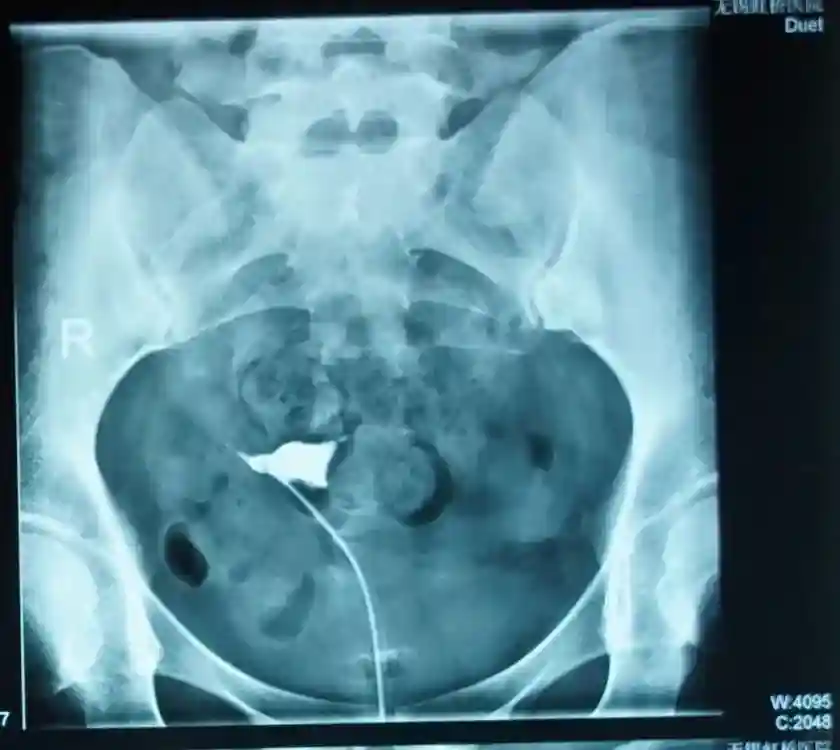

在询问病史时徐祯玉主任得知,2026年李女士曾做过输卵管吻合术。有结扎的病史,又有输卵管手术史,李女士不孕的很大因素可能就与盆腔黏连和输卵管不通畅有关。随后输卵管造影显示,李女士双侧输卵管阻塞。

经过病情评估以及充分沟通后,徐祯玉主任为患者实施腹腔镜下盆腔黏连松解术+宫腔镜下双侧输卵管插管通液术,术后再给予药物调理、恢复输卵管正常的生理机能,帮助李女士尽快怀上宝宝。

复查结果显示,李女士输卵管恢复良好。徐祯玉主任抓住时机,给予李女士促排卵治疗,当B超监测到有优势卵泡发育、成熟、排出的时候,又悉心指导夫妻俩同房试孕,就这样,在试孕的第一个月李女士就成功怀孕。